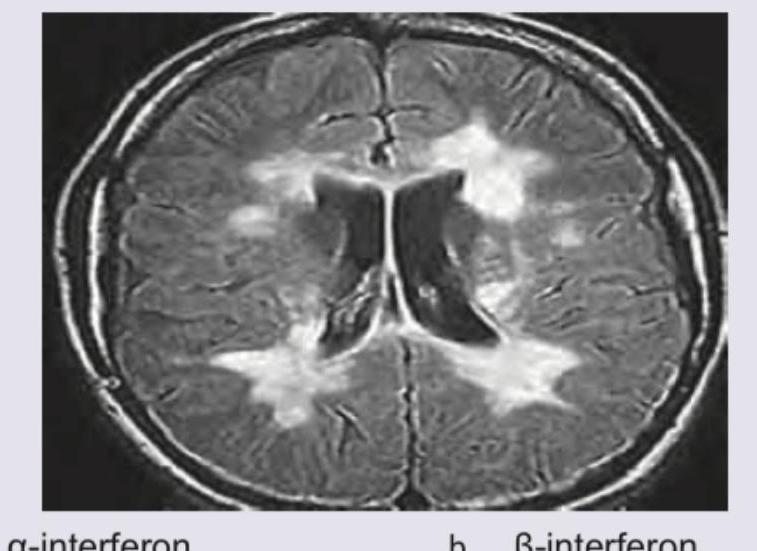

What is the drug of choice for this medical condition showing periventricular lesions?

Explanation: ***β-interferon*** - The MRI image shows **periventricular white matter lesions** which are characteristic of **Multiple Sclerosis (MS)**. - **Beta-interferons (β-interferon)** are a cornerstone in the treatment of **relapsing-remitting multiple sclerosis (RRMS)**, acting as disease-modifying therapies to reduce the frequency and severity of relapses and slow disease progression. *α-interferon* - **Alpha-interferon (α-interferon)** is primarily used in the treatment of certain **cancers** and **viral infections** (e.g., hepatitis B and C), not for demyelinating diseases like MS. - It has a different spectrum of biological activities and clinical applications compared to beta-interferons. *□-interferon* - The option "□-interferon" is not a recognized or standard classification for interferon subtypes in medical or pharmaceutical contexts. - This option is likely a distractor and does not represent a known therapeutic agent for any condition, including MS. *Natalizumab* - **Natalizumab** is a highly effective disease-modifying therapy for MS, but it is typically reserved for patients with **highly active MS** or those who have responded inadequately to other treatments, such as beta-interferons. - While effective, it carries a risk of inducing **progressive multifocal leukoencephalopathy (PML)**, making it a second-line or escalated therapy rather than the initial drug of choice for MS.